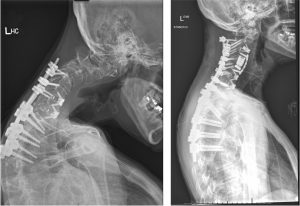

Diorio first began experiencing unexplained neck problems two years ago. Despite worsening pain and visible changes her neck was even starting to bend forward toward her chest, her insurance denied multiple MRI requests. Eventually, after persisting with her neurologist, she received the scan that revealed a rare and serious infection in her bone. Doctors could not determine the exact cause or type of infection, even after extensive testing, but it required immediate treatment.

She underwent emergency surgery, followed by a long course of antibiotics that cleared the infection. Unfortunately, the damage it left behind in her cervical spine caused lasting complications. Julie went through multiple surgeries with different surgeons, but her condition didn’t improve — in fact, at one point it worsened. Finally, she sought out and was referred to Singh, a specialist who could address the complex damage to her neck and spine.

She had lived with these limitations for nearly a year before meeting Singh. She developed a chin-on-chest deformity and could no longer lift her head off her chest. She had to tilt her entire body backward just to look forward. He recommended reconstructive surgery to restore alignment and function. This would involve reconstructing her entire cervical spine to restore her ability to look directly ahead. The operation itself was just the beginning: the path to recovery would take months of healing and commitment.

“The road back would take time a year of follow-ups and patience,” Diorio explains. “I’ve seen him about five or six times since surgery. The follow-ups are so important. He checks that everything is healing correctly, that everything is in place. Each time I see him, I feel reassured.”